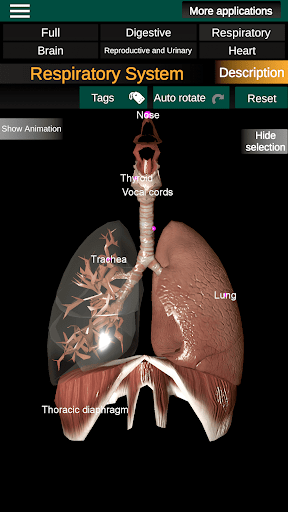

* Respiratory system, which includes the trachea, bronchi, lungs and an animation of this system.

* Easy to access and navigate (zoom, 3D rotation).

* Hide or show information.

* Descriptions of each organ.